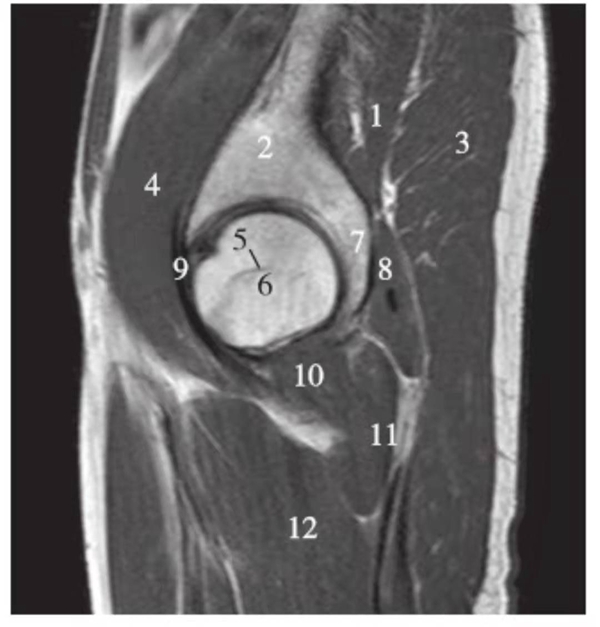

矢状位

正常髋关节经股骨头内缘层面T1WI像

1.髂骨;2.臀大肌;3.圆韧带;4.股骨头;5.坐骨;6.闭孔外肌;7.耻骨肌;8.大收肌